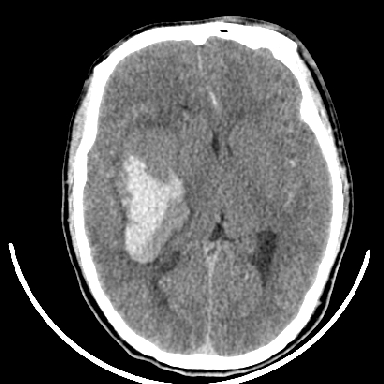

1是高血压性脑出血的好发部位,形态呈肾形,是高血压性脑出血的常见形状

另附部分资料:“血液溢出血管外形成血肿,其内含有大量血红蛋白、血浆白蛋白,球蛋白,因这些蛋白对x线的吸收系数高于脑质,故ct呈现高密度阴影,ct值达40~90h,最初高密度灶呈非均匀一致性,中心密度更高,新鲜出血灶边缘不清。基底节区血肿多为“肾”型,内侧凹陷,外侧膨隆,因外侧裂阻力较小,故向外凸,其它部位血肿多呈尖圆形或不规则形”

支持右侧基底节脑出血

右侧基底节区脑出血.

支持右侧基底节区(主要为外囊区)原发性脑出血。

术中抽出40ml陈旧血液,血肿底部似见一条索血管影